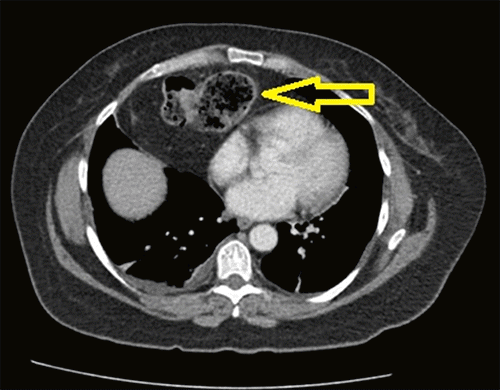

The patient is a 50-year-old woman who presented to the emergency department (ED) with a three-day history of epigastric pain and two days of nausea, vomiting, and obstipation. Her symptoms worsened approximately 12 hours prior to presentation. She reported having undergone a robotic-assisted laparoscopic total abdominal hysterectomy with bilateral salpingo-oophorectomy (TAH-BSO) for a uterine fibroid on the same day the epigastric pain began. Moreover, she also reported having a five-year history of less severe, similar pain, which always resolved spontaneously; she believed this episode would do the same. She appeared in painful distress and showed significant epigastric tenderness upon physical examination. An abdominal and pelvic computed tomography (CT) scan was obtained in the emergency room, demonstrating a right anterior diaphragmatic hernia containing a loop of transverse colon (Figure 1). The defect was further associated with congestion and edema of the antimesenteric border of the herniated bowel (Figure 2).

Figure 1. Abdominal and Pelvic CT Scan. Published with Permission